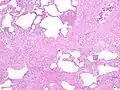

The histologic hallmarks of UIP, as seen in lung tissue under a microscope by a pathologist, are interstitial fibrosis in a "patchwork pattern", honeycomb change and fibroblast foci (see images below).[6][7]

Appearance of usual interstitial pneumonia (UIP) in a surgical lung biopsy at low magnification. The tissue is stained with hematoxylin (purple dye) and eosin (pink dye) to make it visible. The pink areas in this picture represent lung fibrosis (collagen stains pink). Note the "patchwork" (quilt-like) pattern of the fibrosis. Appearance of usual interstitial pneumonia (UIP) in a surgical lung biopsy at low magnification. The tissue is stained with hematoxylin (purple dye) and eosin (pink dye) to make it visible. The pink areas in this picture represent lung fibrosis (collagen stains pink). Note the "patchwork" (quilt-like) pattern of the fibrosis.

Appearance of honeycomb change in a surgical lung biopsy at low magnification. The dilated spaces seen here are filled with mucin. Hematoxylin-eosin stain, low magnification. Appearance of honeycomb change in a surgical lung biopsy at low magnification. The dilated spaces seen here are filled with mucin. Hematoxylin-eosin stain, low magnification.